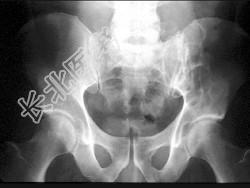

- 单项选择题男,28岁, 左髋疼痛不适三年余,结合图像, 最可能的诊断是 ( )

A、左髂骨动脉瘤样骨囊肿

B、左髂骨单纯性骨囊肿

C、左髂骨骨巨细胞瘤

D、左髂骨棕色瘤

E、左髂骨骨纤维性结构不良